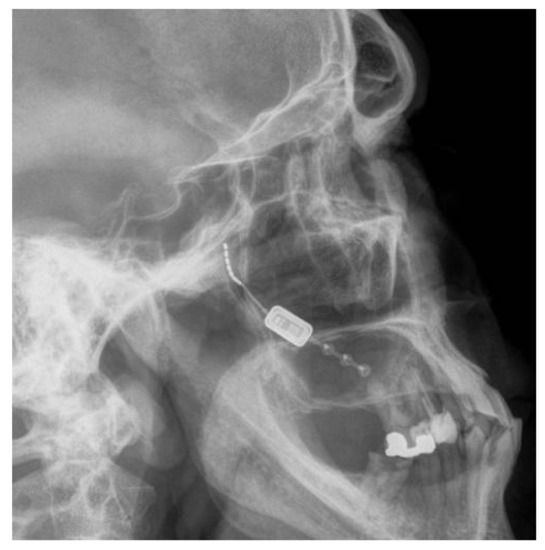

The Pathway CH-2 clinical trial “Sphenopalatine Ganglion Stimulation for Treatment of Chronic Cluster Headache” was an FDA approved study sponsored by Autonomic Technologies, Inc. (ATI), commencing in 2014. It was a multi-center, interventional, randomized, placebo-controlled, parallel, triple-blind safety and efficacy study that included intra-operative procedures for the implantation of the ATI-Neurostimulator in the pterygopalatine fossa so that an active electrode was within 0.5 mm of the sphenopalatine ganglion to intercept cluster headache symptoms at the onset. Each patient signed informed consent approved by the UTSW IRB committee (STU#052015-044). The results of this clinical trial have been previously published [16]. The sphenopalatine ganglion is located at the terminal end of the vidian canal, which contains the greater and lesser petrosal nerves that are preganglionic parasympathetic afferents synapsing in the sphenopalatine ganglion, which are shown to be involved in inducing the trigeminal autonomic reflex onset of cluster headaches [17]. Thus, stimulating the sphenopalatine ganglion would intercept this interaction and terminate the cluster headache. Figure 1 shows a coronal CT scan and adjacent illustration showing the position of the vidian canal (VC) in the medial portion of the pterygopalatine fossa. Just lateral to the VC is the foramen rotundum (FR), which contains the main trunk of the trigeminal maxillary division (V2). The CT view shows visible electrodes properly positioned to stimulate the sphenopalatine ganglion, and the illustration shows the trajectory of the implant close to FR and the transmitter connection on the lateral maxilla. Implantation of the ATI-Neurostimulator is performed through a small surgical incision through the maxillary posterior mucosa to expose the base of the zygoma and the pterygomaxillary plate. An introducer is used to position the implant at the sphenopalatine ganglion site under fluoroscopy. Figure 2 shows an illustration of the introducer device used to position the ATI-Neurostimulator. The electrodes are inactive during placement and only stimulated after the implant has been fixated. The TCR events precede activation, thus, the proposed mechanism of TCR induction is a mechanical interaction with V2 near the FR during use of the introducer device and subsequent positioning of the implant for fixation. Figure 3 shows a lateral CT view of an ATI-Neurostimulator after fixation.

Figure 3. A lateral radiograph showing the proper position of an ATI-Neurostimulator with electrodes within the pterygopalatine fossa and fixation to the posterior maxillary buttress.